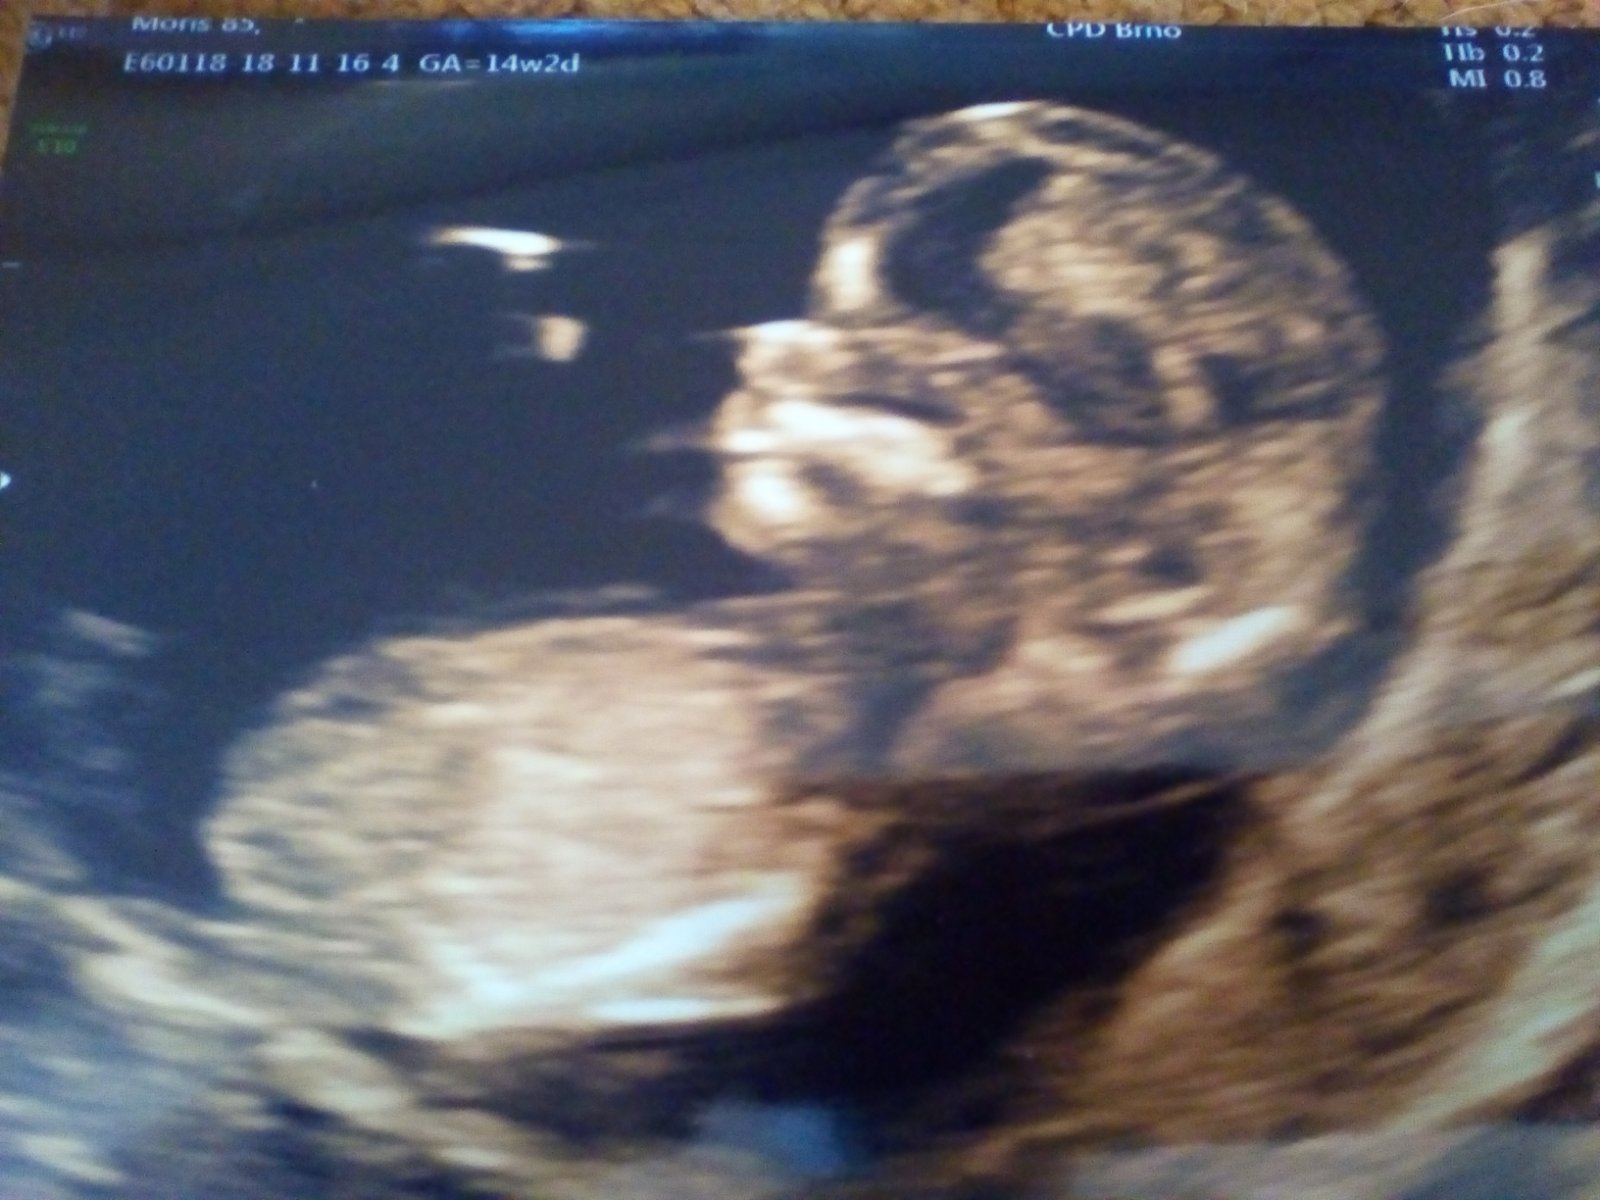

@jennas ahoj, gratuluji k ms !!je já to mám takové šílené,v pondělí hospitalizace kvůli masivnímu krvácení,jela jsem tam s tím že je konec,no máme bojovníka/ci,ustalo to,praskl mi hematom,krve jak když otevřete kohoutek,pořád tam něco mám,takže ležím a ležím,ve čtvrtek mě neradi propustili z nemocnice abych mohla v pátek na screening,jela jsem tam s hrůzou a navíc jsem stále spinila,no čekáme zdravé mlade,je to živel,dnes už ani nespinim ale hematom pořád mám,takže si v leze ještě pobudu a ve čtvrtek kontrola,snad už máme zle vybrané a miminko bude bojovat dál,foto 14tt že screeningu